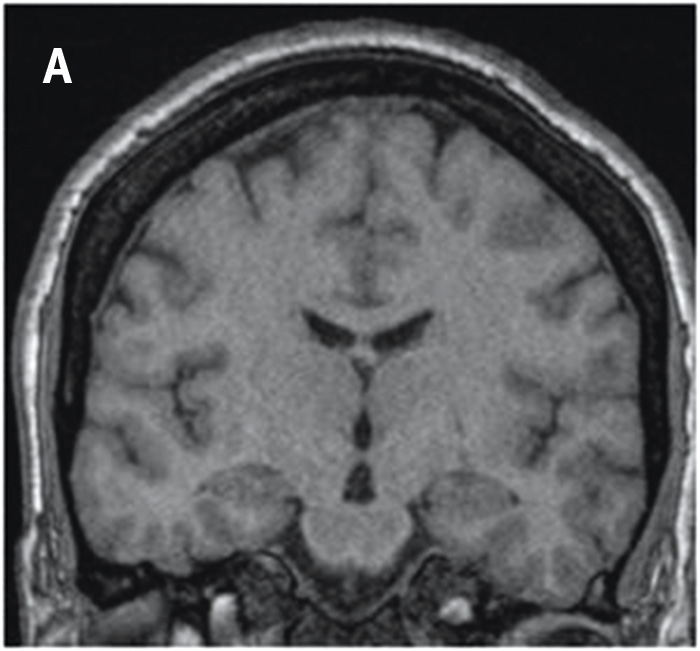

Bedömningen sker enligt en femgradig skala, 0–4, där MTA 0 och MTA 1 visar normala förhållanden och MTA 2–4 ökande grad av atrofi. MTA 2 är patologiskt hos patienter yngre än 70 år och MTA 3 är patologiskt hos alla patienter under 80 år, medan MTA 4 alltid måste uppfattas som patologiskt oavsett patientens ålder (Figur 1) [15].

Figur 1. MTA-graderna 0 (A), 1 (B), 2 (C), 3 (D) och 4 (E).